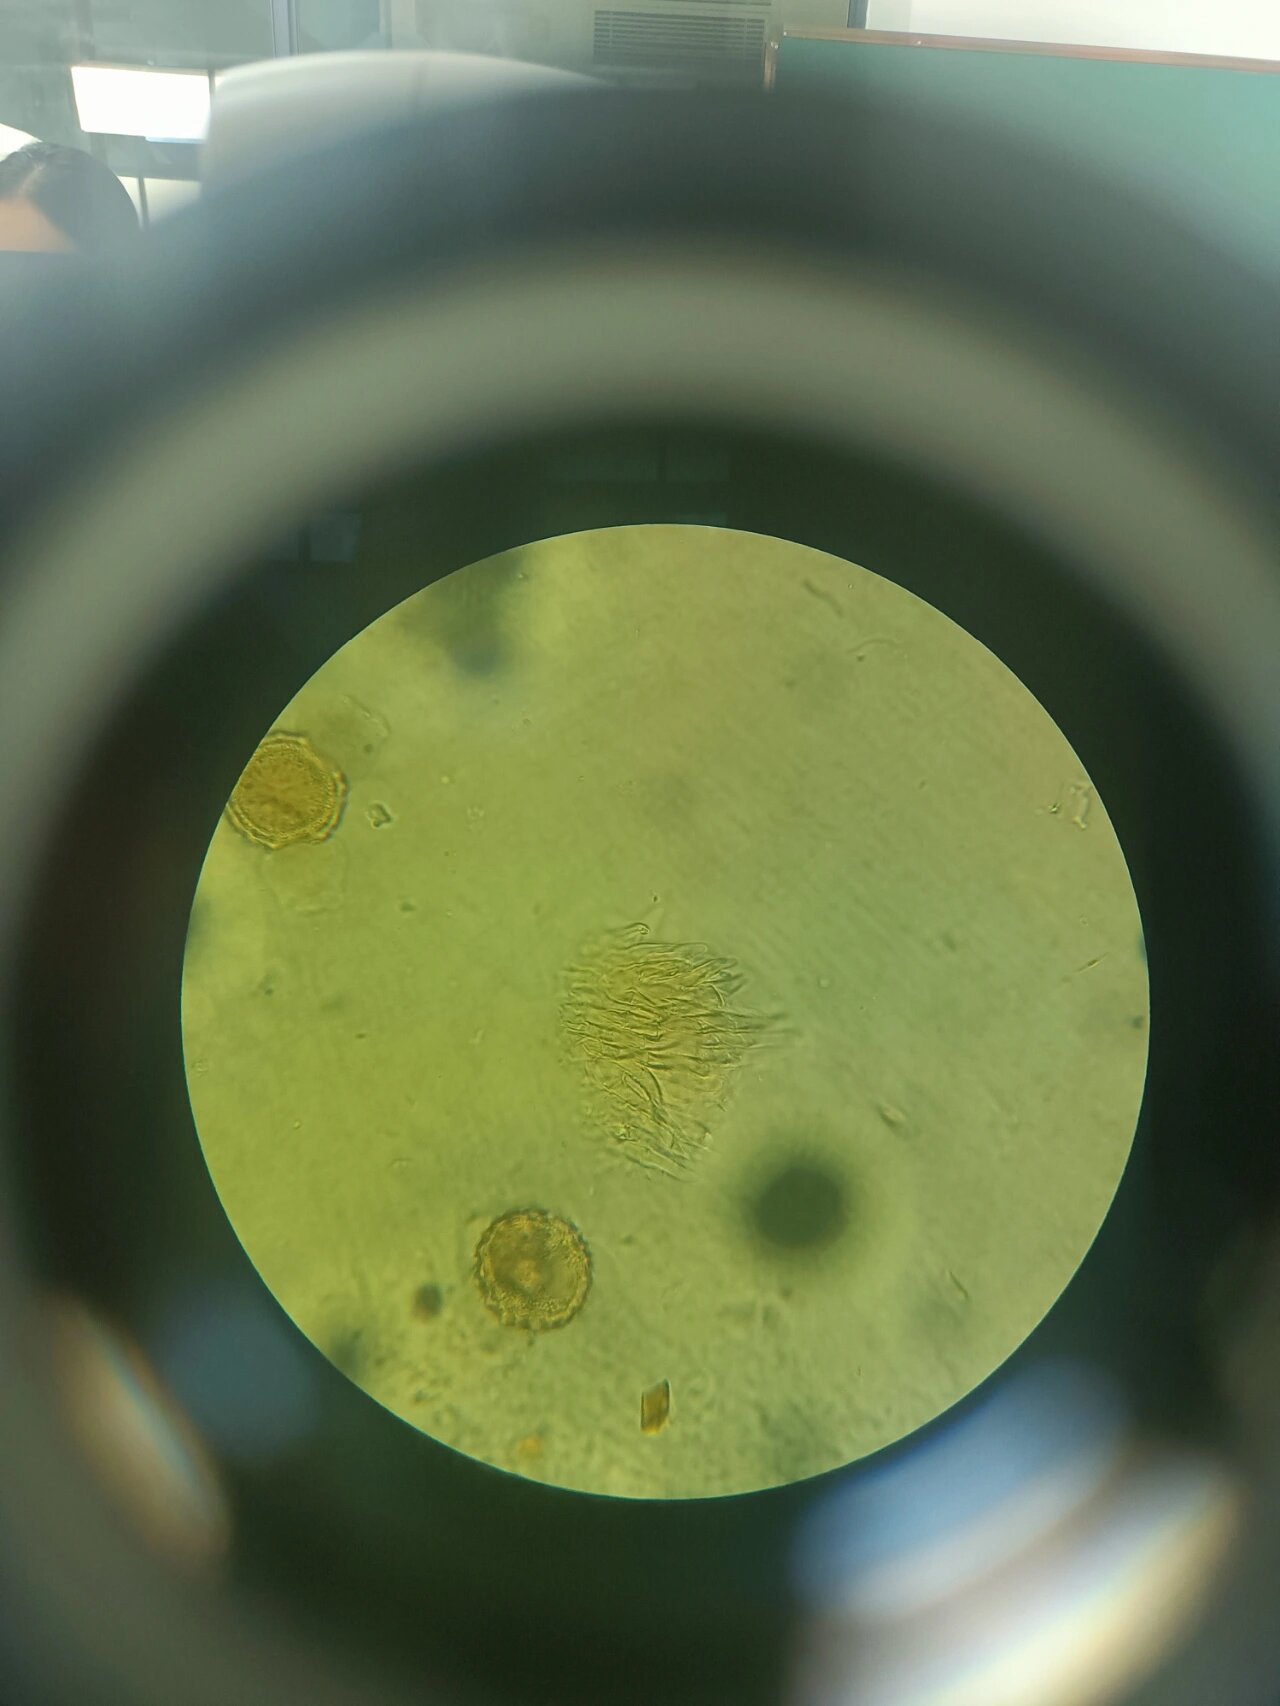

红花粉末显微鉴别 1花粉粒 2长管道状分泌细胞 3花柱碎片

p>红花的显微鉴别特征 br>1.花粉粒 br>2.分泌细胞 br>3.

中药红花的显微特征 1,花柱碎片 2,花粉粒 3,分泌细胞